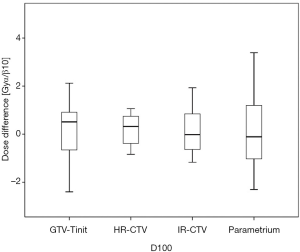

Among the 23 patients included in the present study, the mean tumor diameters were 68.35 cm3 at diagnosis and 29.63 cm3 at ICBT initiation. The mean tumor regression was 56.6%. The mean ± standard deviation (SD) HR-CTV D90 and D100 of the GTV-Tinit, IR-CTV, and parametrium were 69.58±4.94, 61.89±3.53, 54.16±4.01, and 55.71±2.73 Gyα/β=10, respectively, for DIR and 69.11±5.68, 61.55±4.15, 53.99±3.93, and 55.51±2.27 Gyα/β=10, respectively, for the conventional simple DVH parameter addition (Figures 3-5). No statistically significant differences were observed in the dosimetric parameters between the two calculation methods (Table 2). No systematic differences were observed between DIR-based accumulation and DVH parameter addition (P=0.11).

Contouring and reconstruction performed in the same image series allowed the dose to targets and organs to be directly calculated without any image fusion. However, the fusion uncertainties could translate into absorbed dose calculation when several image series were combined. For example, contouring was performed in one image series and reconstruction in another. Tanderup et al. reported that uncertainties resulted in a miscalculation of DVH dose parameters by typically 4% to 6% mm−1 of fusion error between CT and MRI (18). van Heerden et al. (19) recently used DIR to determine the absorbed dose distribution of daily image-guided adaptive EBRT and brachytherapy. The cone-beam CT of the first EBRT fraction and the brachytherapy planning MRI were registered by DIR. The cumulative dose to 2 cm3 with the highest dose (D 2 cm3) from EBRT and brachytherapy to the bladder and rectum were calculated and compared to those for direct addition, assuming a uniform EBRT dose (UD). The differences between UD and DIR were less than 3.9 GyEQD2. Our study only used CT images with the same field of view and slice thickness for fusion. The DIR-based DVH parameter values did not differ significantly from those derived from the conventional simple DVH parameter addition (Figure 3). According to the Groupe Européen de Curiethérapie and the GEC-ESTRO recommendations (10), the conventional simple DVH parameters for the target volumes and OARs in EBRT and each ICBT session were simply added to estimate the cumulative DVH parameters.